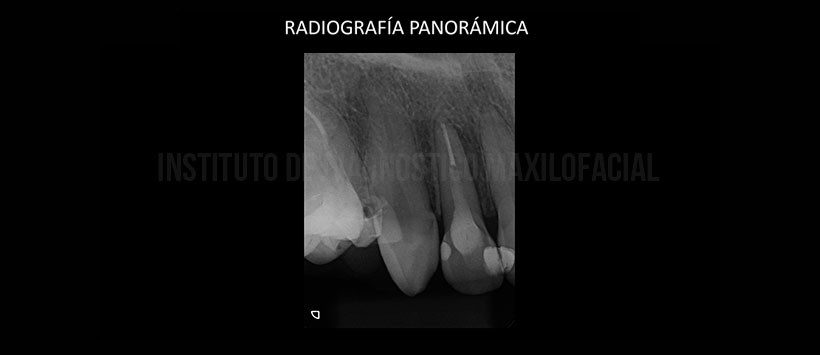

A la evaluación de la radiografía panorámica, se evidencia la presencia de múltiples piezas con material de obturación de conductos, espigo, coronas protésicas, así como múltiples piezas ausentes (Figura 1). Posteriormente se obtuvo una radiografía periapical de la zona a evaluar, donde visualizo que la pieza 12 presenta material de restauración en zonas proximales, aparente espigo de material radiopaco y material de obturación de conducto. Cabe resaltar la ausencia de lamina dura en mesial de la en mención, así como una aparente disminución de la densidad ósea de ese mismo lado. (Figura 2)